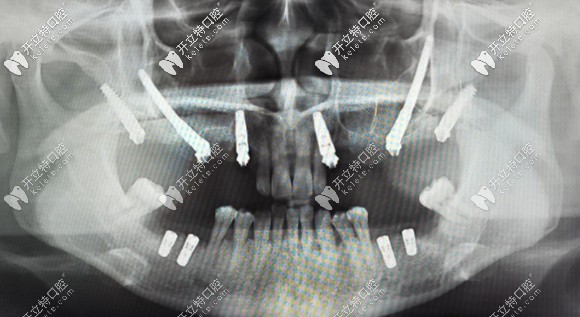

簡(jiǎn)單來(lái)說(shuō),把種植體植入到顴骨和翼板骨上的種植方法,就叫做穿顴穿翼種植技術(shù)。

對(duì)于上頜骨切除、上頜骨重度萎縮,做常規(guī)的上頜竇內(nèi)外提升,也沒(méi)有辦法達(dá)到種植條件的無(wú)牙頜患者,就需要向頜面部的顴骨和翼板找可植入種植體的骨頭。

而這部分的骨頭也適合作為種植位點(diǎn),它不會(huì)像牙槽骨那樣萎縮吸收。但是,也由于這個(gè)位置比較靠上,所以,手術(shù)的難度也就大大增加了,一般的口腔機(jī)構(gòu)都無(wú)法進(jìn)行這項(xiàng)手術(shù)。

穿顴穿翼就是種植體植入到顴骨和翼板骨上的種植方法